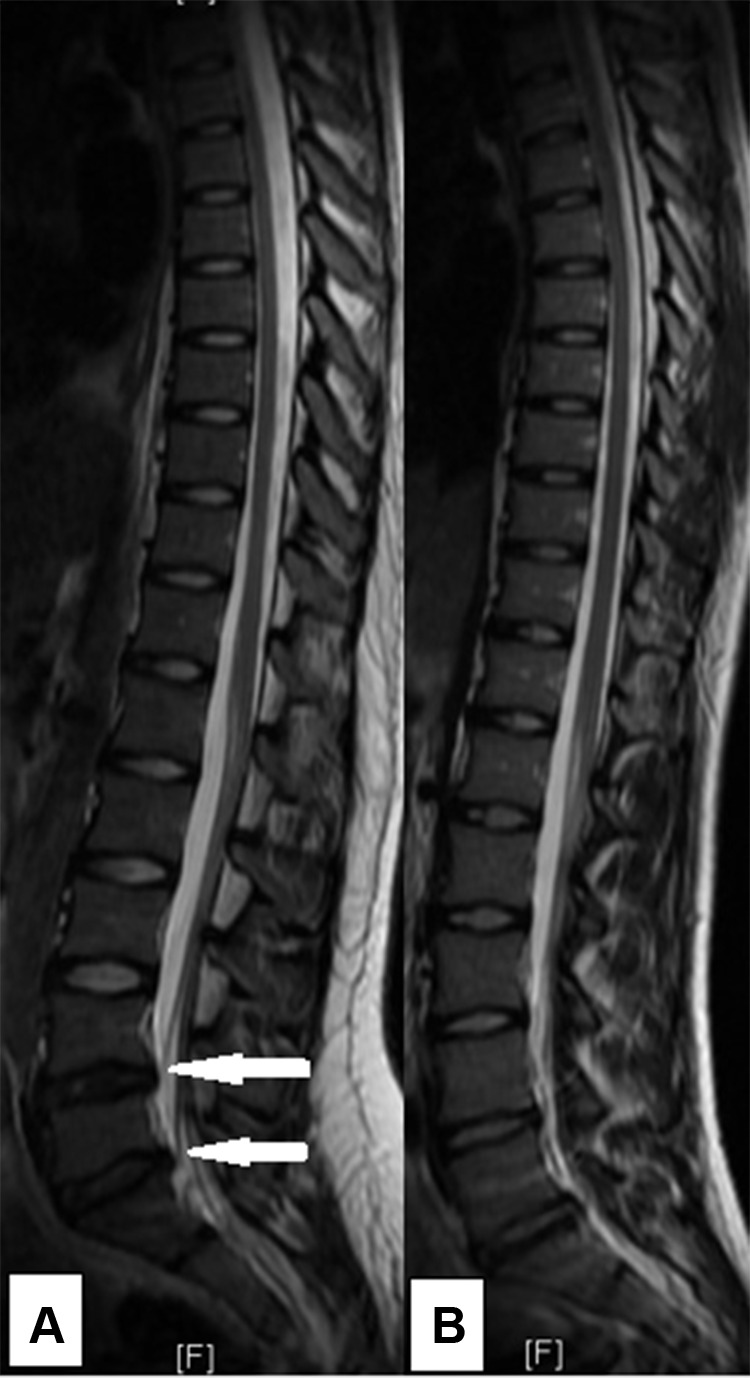

Methods: MRI of the thoraco-lumbar spine was performed on 30 skiers (mean age 20 years, female 43%) and 16 non-athletes (mean age 19, female 75%), available for the 2-year follow-up. The intervertebral discs were evaluated for signal, height, bulge/herniation, and additionally according to Pfirrmann classification, and the endplates were graded according to endplate defect score. Any of the following disc findings was defined as disc degenerative change: reduced signal, reduced height, bulge, or herniation. All participants answered a specific back pain questionnaire.

Results: No significant difference in spinal column abnormalities, nor back pain, was found between baseline and 2-year follow-up in neither skiers nor controls. There was significantly higher prevalence of disc degenerative changes in skiers (73%) than in non-athletes (44%, p=0.05). Skiers (63%) had significantly more Pfirrmann grade ≥3 discs compared to non-athletes (25%) (p=0.03). There was no significant difference in number of endplates with score ≥4 between skiers and non-athletes (50% vs 38%, p=0.40) nor in lifetime prevalence of back pain between skiers (46%) and non-athletes (40%).

Conclusion: There was no significant change over time of the spinal column MRI abnormalities, nor back pain prevalence, during a 2-year follow-up of skiers and non-athletes. Young skiers had significantly higher prevalence of spine abnormalities compared with non-athletes. There was no significant difference of the back pain lifetime prevalence in skiers compared with non-athletes.